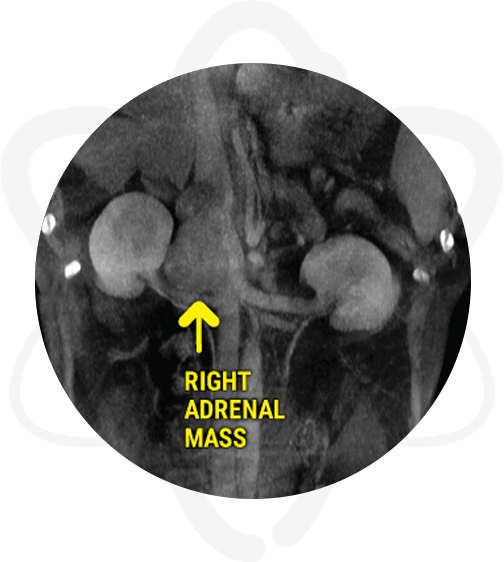

Patient is a 14 yr old, MN, retriever mix that presented for a brain CT due to recent onset of lethargy, ataxia, not eating well and abnormal behavior. In addition, a CT scan of the abdomen was requested due to an adrenal tumor found on ultrasound.

- Abdominal ultrasound revealed an enlarged right adrenal gland of mixed echogenicity, solid in appearance, irregular in shape but with no evidence of mineralization.

A large aggressive right adrenal mass invading the caudal vena cava and displacing the right kidney and renal vessels was noted on abdominal scan. The mass likely represents a neoplastic process such as adrenocortical carcinoma or pheochromocytoma vs neuroendocrine neoplasia. The slim left adrenal may be secondary to some degree of atrophy. No other evidence of metastasis was noted. In addition, there were portal vein filling defects which can be secondary to small thrombi or secondary to streamlining (artifact of flow).

Provided crucial information such as invasion into vena cava and displacement of right renal vessels regarding the previously known adrenal gland abnormalities.

When suspecting hyperadrenocorticism, performing a CT scan of the abdomen provides valuable information to help differentiate PDH vs ADH. In cases of adrenal masses (ADH), the HD CT scan enables the clinician to have important information regarding the size of the mass, adjacent vascularity, resectability potential, and staging. Furthermore, thoracic CT is also recommended to screen the pet for metastatic disease. Similarly, in cases of PDH, in addition to the abdominal CT, performing a head CT during the same procedure will allow evaluation of the pituitary gland to screen for macroadenomas.